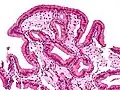

Micrografia da colesterolose da vesícula biliar.